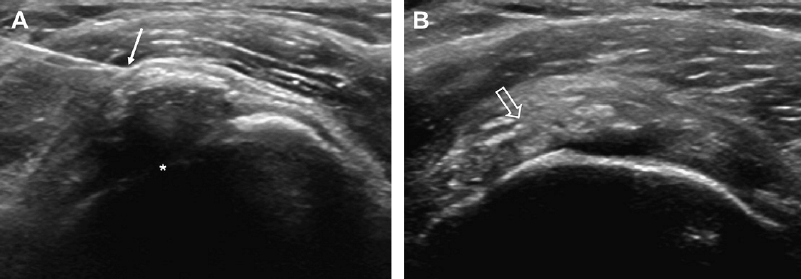

Kalcinirajoči tendinitis ramena je stanje, pri katerem pride zaradi kalcinatov v tetivi do vnetja v ramenskem sklepu. Kristali kalcija se nalagajo v slabo prekrvljenem delu tetiv in povzročajo vnetje v ramenu, ki se kaže kot vnetje ovojnice ali kot vnetje subakromialnega mešička. Bolniki opisujejo močno bolečino in omejeno gibljivost v ramenu.

V kolikor so kalcinati večji od 8mm in so enakomerne strukture lahko pod ultrazvočno kontrolo opravimo tudi punkcijo kalcinata in kalcinat izperemo. Poseg se opravi v lokalni anesteziji in traja približno 30 minut. Bolečina lahko traja tudi nekaj dni po posegu. V teh primerih svetujemo jemanje analgetikov. Nekaj dni po posegu priporočamo postopno stopnjevanje aktivnosti, izvajanje vaj, plavanja, nordijske hoje in fizikalne terapije in po 2 -3 mesecih vrnitev željenim aktivnostim.